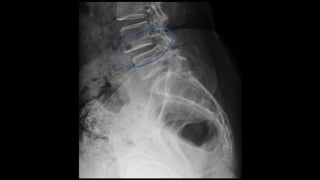

Investigation

• Xray

• MRI

• CT myelogram

• EMG, SSEPs, NCS